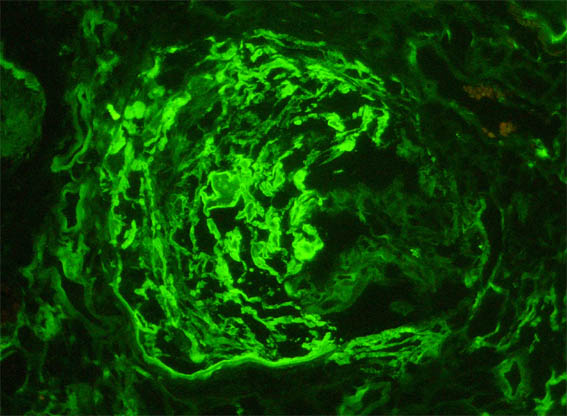

Figura 12. Inmunofluorescencia directa para fibrinógeno, X400.

Inmunofluorescencia para IgA, IgM y C1q: Negativas.